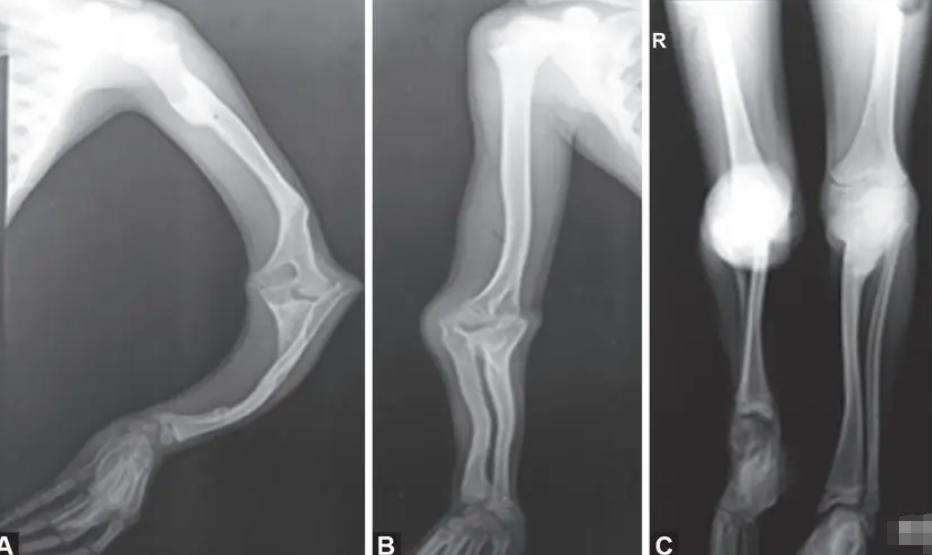

1986年,创利出生证广东汕头里的一个偏僻农村,但不同于健康的小孩, 创利从出生就被判处了终身残疾, 医生告诉创利父母, 他患有玻璃症,学名叫先天性脆骨病,这种病会让小孩经常处于骨折状态,身体机能不会发育完善并且现在还没有治愈的办法。

但是毕竟创利是个玻璃症孩子,骨头稍微用力就会断掉。一年寒冬,盖着两张厚被子的创利一个翻身后手脚骨折。和朋友们一起打球时接了下球手也骨折,甚至有时候走着走着也会骨折,渐渐地,身边的小伙伴都不敢和创利一起玩,创利的内心也开始封闭起来。